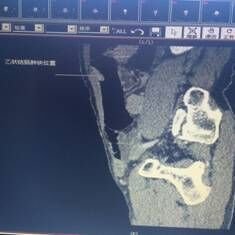

我院胃腸外科今年3月收治一名男性患者,以反復(fù)腹痛7月入院,CT提示胃竇部及乙狀結(jié)腸占位性病變(分別見圖1、2),行內(nèi)窺鏡活檢分別考慮胃腺癌以及乙狀結(jié)腸絨毛狀腺瘤,不排除惡變傾向。為改善患者生存率,減少創(chuàng)傷,手術(shù)團(tuán)隊(duì)決定充分發(fā)揮腹腔鏡技術(shù)優(yōu)勢,采用腹腔鏡下一期同時(shí)切除胃、結(jié)腸病變,由于患者乙狀結(jié)腸病變惡性診斷不明確,根據(jù)腫瘤根治的原則,先處理乙狀結(jié)腸。手術(shù)當(dāng)中依據(jù)冰凍切片,在腹腔鏡下首先完成乙狀結(jié)腸癌根治,后行腹腔鏡下遠(yuǎn)端胃癌根治術(shù)。一次微創(chuàng)手術(shù),切除兩個(gè)腫瘤,免除了患者傳統(tǒng)剖腹手術(shù)及二次手術(shù)的創(chuàng)傷,縮短了住院時(shí)間,術(shù)后恢復(fù)快,降低了患者住院費(fèi)用。

圖片1                               圖片2